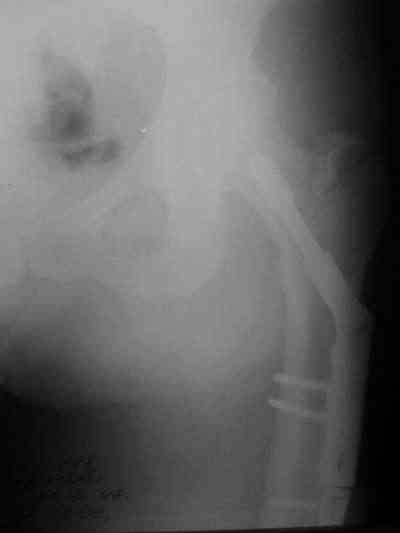

Около 10 дней назад выполнил остеосинтез бедренной кости LC-DCP и DHS по поводу фрагментарного оскольчатого перелома в средней трети и чрезвертельного перелома.

Снимки в приложении.

В приложении и имеющийся в наличии брейс. Приношу извинения за низкое качество снимков.

Качество снимков приемлемое. С нагрузкой категорически не надо спешить - только при уверенных рентгенологических признаках сращения на обоих уровнях в данном случае. Т.е. не только на диафизе, но и в вертельной области. При безупречном синтезе DHS ранняя нагрузка в этой зоне была бы безопасна, все определялось бы сращением диафиза. А поскольку винт в DHS сделали ну о-очень короткий, то ойкнуть не успеете, как

проксимальный отдел бедра в варус кувыркнется.

Уважаемый Никита, очень меня расстроило не качество снимков, а сам остеосинтез. Вертельный перелом, пожалуй, еще срастется. А диафиз может преподнести ожидаемое, предуготованное осложнение: несращение и перелом импланта, даже если это суперфмрменная пластина.:(